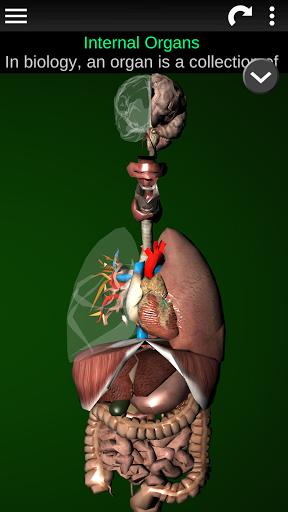

Menampilkan model anatomi 3D dari organ utama tubuh manusia dan penjelasannya masing-masing.

Apa yang ada di aplikasi?

* Sistem pencernaan, termasuk lambung, usus kecil, usus besar, dan animasi sistem ini.

* Sistem pernafasan, yang meliputi trakea, bronkus, paru-paru dan animasi sistem ini.

* Otak, yang meliputi otak, otak kecil, dan batang otak.

* Jantung, yang meliputi atrium, ventrikel, aorta, dan animasi organ ini.